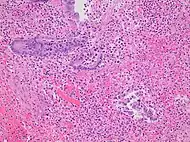

Pathology

Even for clinically certain appendicitis, routine histopathology examination of appendectomy specimens is of value for identifying unsuspected pathologies requiring further postoperative management.[69] Notably, appendix cancer is found incidentally in about 1% of appendectomy specimens.[70]

Pathology diagnosis of appendicitis can be made by detecting a neutrophilic infiltrate of the muscularis propria.

Periappendicitis (inflammation of tissues around the appendix) is often found in conjunction with other abdominal pathology.[71]

Micrograph of appendicitis and periappendicitis. H&E stain

Micrograph of appendicitis showing neutrophils in the muscularis propria. H&E stain

Acute suppurative appendicitis with perforation (at right). H&E stain